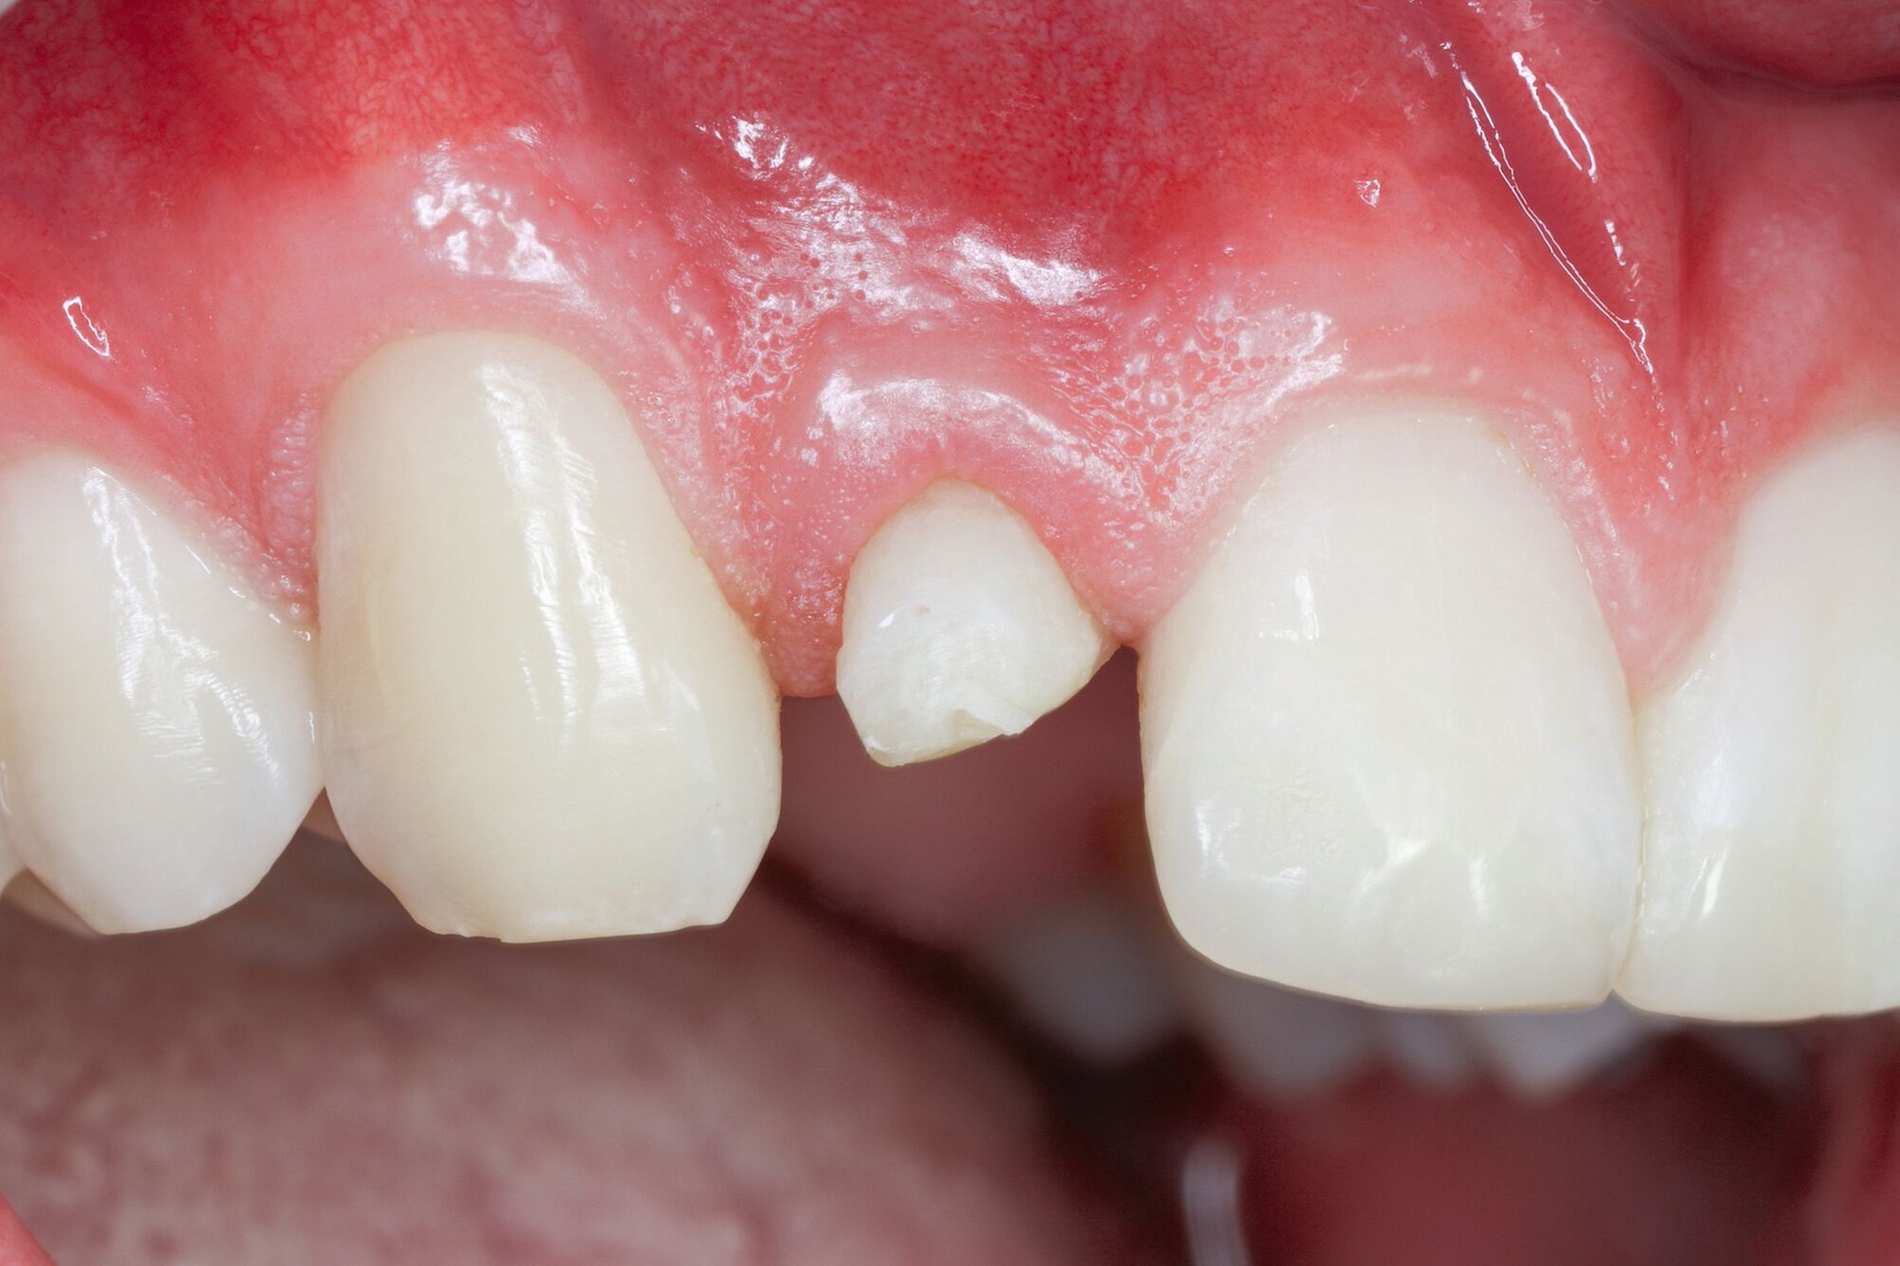

Die adhäsive Wiederbefestigung mitgebrachter Kronenfragmente bietet sich als einfache und konservative Methode zur Wiederherstellung von Funktion und Ästhetik an (Abbildung 1). Wenn das Fragment nach dem Unfall unter feuchten Bedingungen gelagert wurde, wird die Wiederbefestigung idealerweise sofort während der Notfallbehandlung durchgeführt. Wurde das Fragment jedoch durch eine längere Trockenlagerung dehydriert, sind sowohl das ästhetische Ergebnis als auch die Komposithaftung kompromittiert. In solchen Fällen wird eine Lagerung in physiologischer Kochsalzlösung oder in Wasser für einen Tag empfohlen, um eine Rehydrierung des Fragments zu ermöglichen [Farik et al., 1999], während das Dentin in der Zwischenzeit mit einem leicht entfernbaren temporären Material bedeckt ist (zum Beispiel Kalziumhydroxid-Zement). Die Rehydrierungszeit kann durch eine feuchte Lagerung des Fragments in einem sauberen Drucktopf auf 30 bis 60 Minuten verkürzt werden.